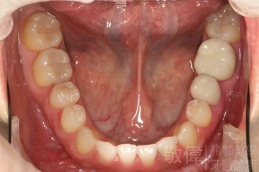

變臉矯正,原來戽斗妹跟大歪臉變成自信正妹

經由本院3D數影X光影像儀分析、與3D齒顎顏矯正技術,再配合口腔顎面正顎專科醫師施以正顎手術治療,雙方共同合作,使患者臉部外觀有很好的改善,大歪變小歪,產生了天南地北的大改變,她的人生也整個變得不一樣。

因為矯正與正顎手術的配合,使「戽斗妹」變成了「陽光正妹」,完全的改變了她的人生,在面對各種場合、與人交際都散發出自信微笑。所以,奉勸家長,如果小朋友有臉顎畸型的問題,應該考慮配合做這種簡單、安全、有效的正顎手術。

「3D齒顎顏矯正」,不止矯正您的牙齒,也會改變您的人生。「治療前」和「治療後」出社會的人生際遇一定會截然不同。